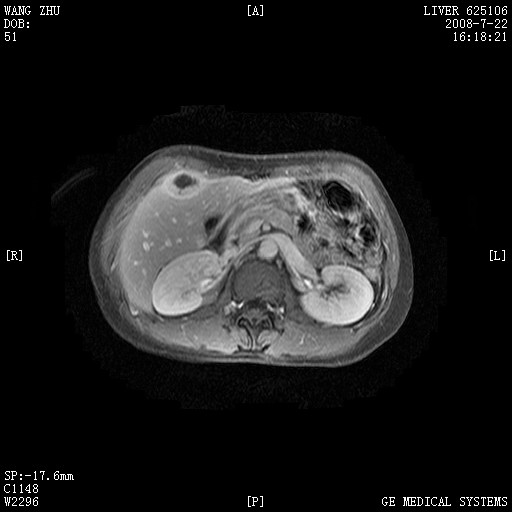

图像有点乱,病灶边缘清楚,可见纤维囊壁,灶旁可见异常灌注,增强显著增强,病灶有早期完全充填,无快退征像,考虑炎性病灶,肝结核可能性大,不知有何病史

肝前外缘见一类圆形囊性病灶,边缘强化,灶周肝为炎性渗出改变,其肝周可见少量腹水,符合炎性病变,病史较长---考虑腹膜结核。肝为外压性改变,脾为动脉期改变。